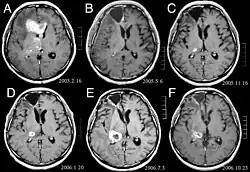

Gwiaździak anaplastyczny (łac. astrocytoma anaplasticum, ang. anaplastic astrocytoma) – nowotworowy guz mózgu. Jest guzem o wysokiej złośliwości (III° według WHO). Nieleczone guzy tego typu w znacznej części przypadków ulegają progresji do glejaka wielopostaciowego.